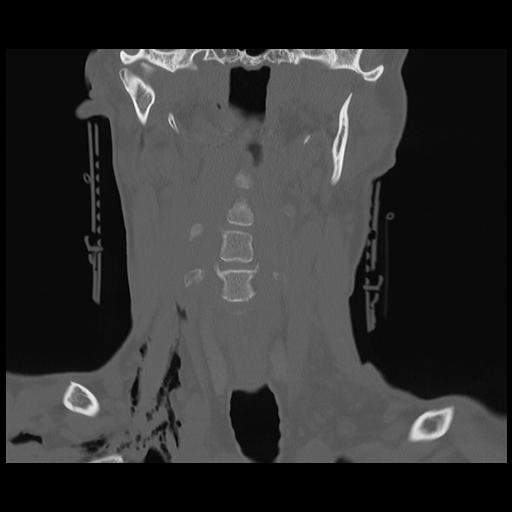

16 HUESO,,Coronal,2.000,HUESO,Coronal,